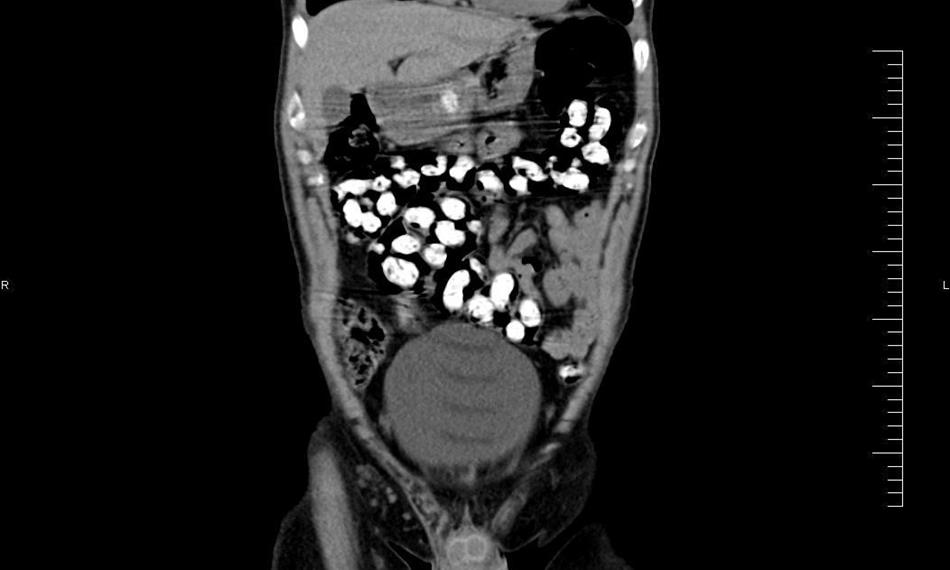

Ke kontrole byl polykač celníky vytipován na základě provedené rizikové analýzy daného letu. Prvotní podezření na pašování drog celníkům potvrdily kontrolní stěry z rukou pašeráka.  Při důkladné kontrole jeho zavazadel a osobní prohlídce nebyly drogy nalezeny, proto bylo provedeno následné rentgenové vyšetření (viz.foto).

Postupně z těla pašeráka vyšlo všech 107 kontejnerků naplněných tuhou hmotou černé barvy. Chemická látka při provedení detekční zkoušky pozitivně reagovala jako opiát. Celková hmotnost všech kapslí včetně drogy je 856 gramů. Určení vlastní hmotnosti a druhu zajištěné drogy je předmětem další odborné expertízy. Podle zkušeností celníků se s největší pravděpodobností jedná o surové opium. Tento druh drogy není na českém trhu obvyklý a zřejmě byla určena k distribuci v jiné zemi.